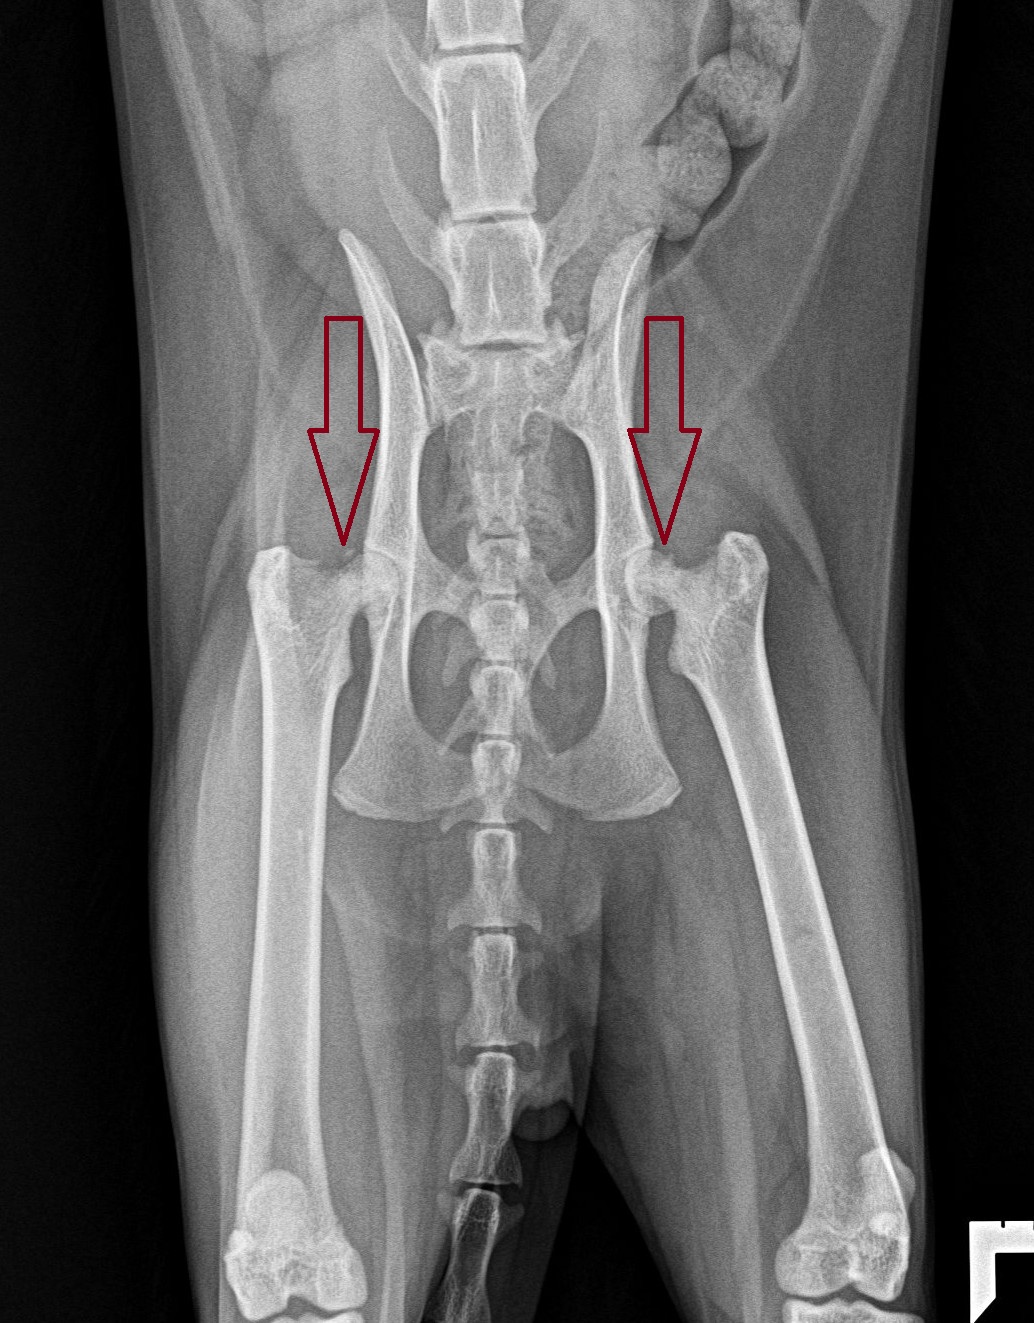

A shocking finding on X-rays

Their family vet took X-rays of his back and hips. He was started on anti-inflammatory drugs and antibiotics, “which didn’t really make any difference over the course of about 10 days.”

Atlas was then referred to LRVSS, where X-rays confirmed that Atlas had broken both of his hips!

The fancy medical name of this type of fracture is “slipped capital femoral epiphysis.”

It can happen in one hip of both, and at the same time, or over time.

Studies profoundly disagree on how often the fractures happen in both hips at the same time, from 20% to 90% of the time!

Bottom line: “If a kitty has this in one hip, there is a 30% to 40% chance both are already affected. Even if the other hip looks OK today, it is likely to fail within the next few months because it’s now carrying all the weight.”